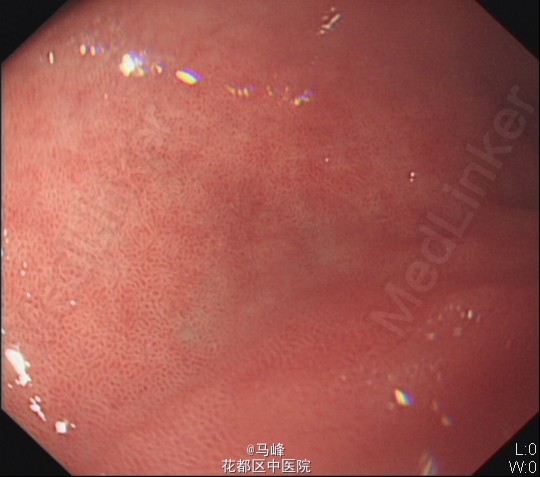

老年男性,主诉:发现乙肝肝硬化7月,返院复查。既往有乙型肝炎病史,目前已服用“博路定 0.5mg qn”抗病毒治疗4月。 现病史:患者7月前外院诊断“乙肝肝硬化”。后为求进一步诊治,来我科住院治疗,分别于2014-9-9、2014-10-21及2015-3-20在我院行胃镜下“食管重度静脉曲张套扎术”治疗,术后无诉不适,好转出院。

入院后予抗病毒、补充营养等对症支持治疗,排除禁忌症后于13/5在无痛胃镜下行食管重度静脉曲张套扎术,术后予加强护胃治疗。